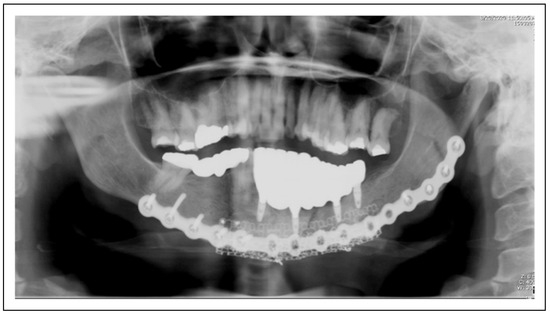

Figure 2.

Patient 12 is restored with 4 mandibular implants that support the dental prosthesis. The implants remain stable and without pathology after 12 months.